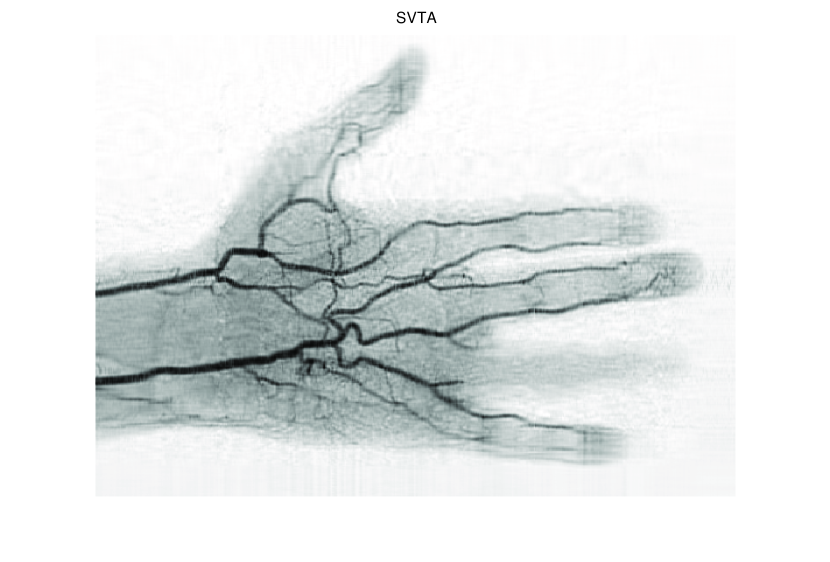

In this section, we first present numerical results of ISVTA for matrix completion problems, and then compare it with some state-of-art methods (singular value thresholding algorithm (SVTA) and singular value projection algorithm (SVPA) respectively proposed in [11] and [31]) for image inpainting problems. Numerical experiments on matrix completion problems show that our method performs powerful in finding a low-rank matrix and the numerical experiments about image inpainting problems show that our algorithm has better performances than SVTA and SVPA. Among all of the experiments, differing from the Scheme 2, we set , and

5.2 Image inpainting

In this subsection, we demonstrate performances of ISVTA on image inpainting problems. The ISVTA is tested on some medical grace images ( Brain angiography image (BAI), Hand angiography image (HAI) and Intracranial venous image (IVI)). We use the SVD to obtain their approximated low-rank images with rank , respectively. Numerical results of ISVTA for theses low-rank image inpainting problems are reported in Table 5, 6, 7, 8.

Table 5, 6 show that ISVTA performs powerful in finding a low-rank matrix on image inpainting problems. Indeed, we could get an exact low-rank image by the ISVTA by choosing proper . Moreover, it is necessary to point out that our method does not work well for all , and we can find that is not a good strategy for the low-rank IVI either or . The numerical results of ISVT, SVTA and SVPA compared in Table 5, 6, 7, 8, 9, 10 under same circumstance show that the ISVT algorithm performs far more better than ISTA and SVPA on image inpainting problems for some proper .